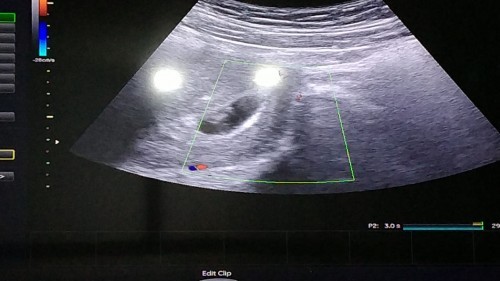

Kehamilan 2 bln 2 hari

Assalamualaikum bunda...alhamdulillah mlm ini saya sudah periksa ke dokter kandungan, dan hasil usg yg skrg tidak sama dg yg kmrin periksa ke bidan. Hasilnya pun ga terlihat ada pendarahan..dan hasil hpl nya ga sama dg yg periksa ke pus dan bidan. Kalau dari pus dan bidan terhitung 7minggu kalau dokter terhitung baru 16 day dilihat dari hasil usg. Seneng banget karna terlihat jantung mau tumbuh🥺 terimakasih ya buat yg sudah doain dan memberi saran kemarin🙏 semoga bunda2 semua yg sdg mengandung sehat2 lancar sampai persalinan❤️